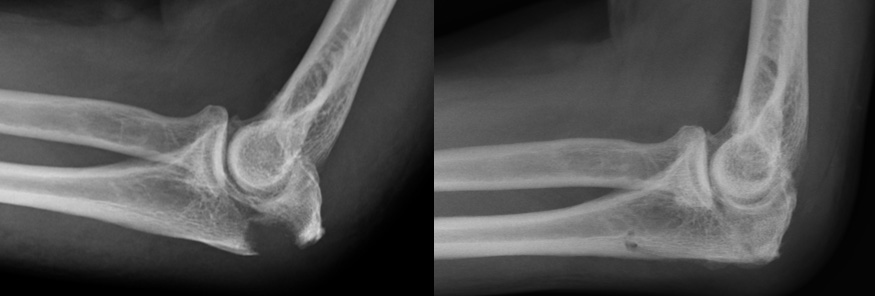

Displaced Olecranon fracture (left). Same elbow healed after suture-only fixation (right)